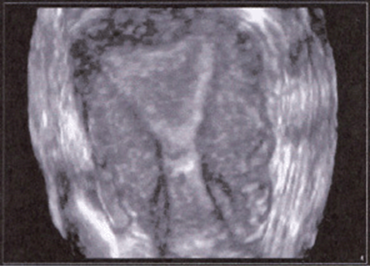

FIGURE 8–17. Multiplanar image of normal fetal spine. (Courtesy of Philips Healthcare.)

FIGURE 8–18. Multiplanar image of normal sacrum of a fetus at 26-weeks’ gestation. (Courtesy of Philips Healthcare.)